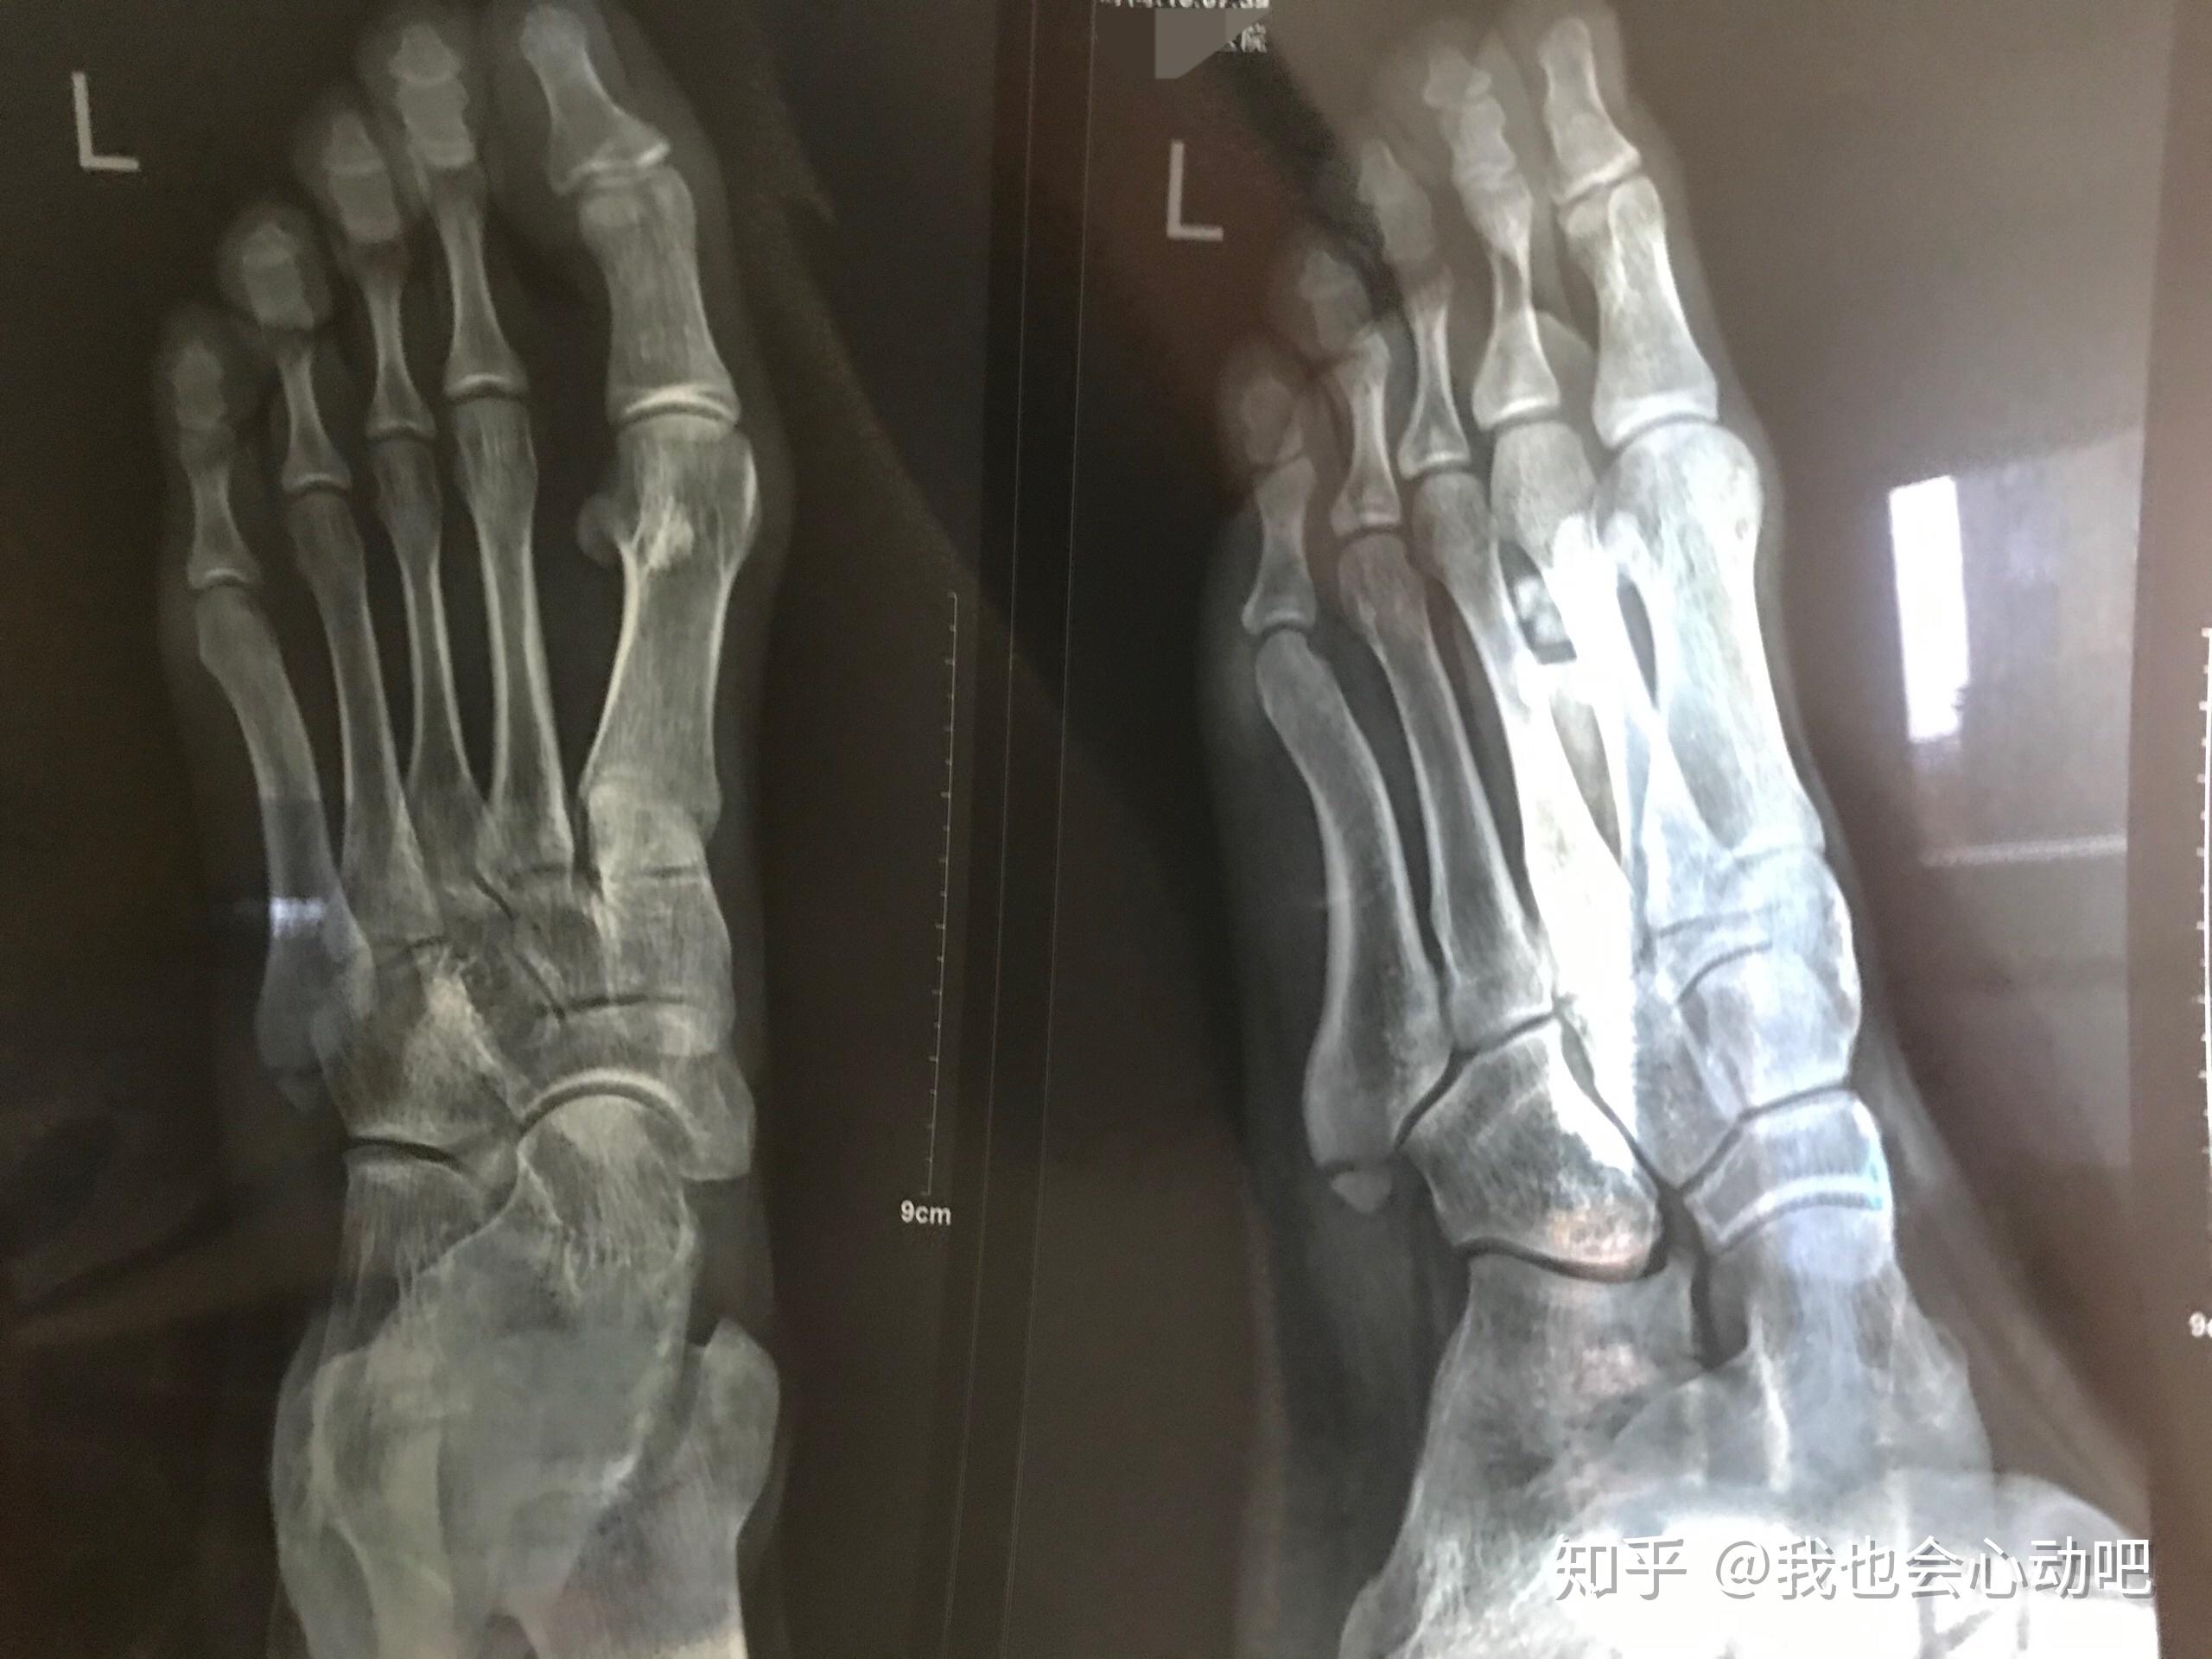

左脚跖骨第五基地骨骨折

7月23日跑步时不小心是去平衡左脚崴了一下,当时

各位觉得左脚第四跖骨基底有无问题?